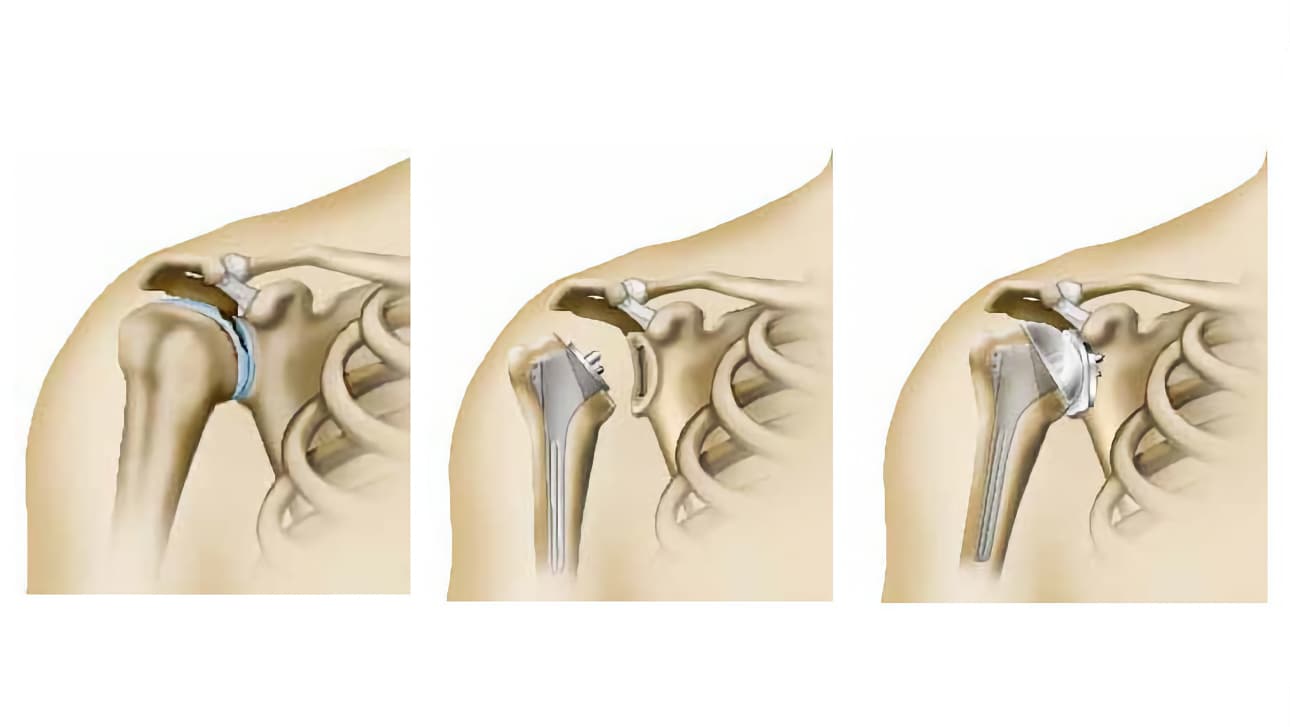

Υπάρχουν πολλές χειρουργικές τεχνικές. Οι κύριες μέθοδοι που μπορεί να εφαρμοστούν, περιλαμβάνουν:

- είτε την ενίσχυση του οστού της ωμογλήνης (με την αποκατάσταση ή την οστική προσθήκη),

- είτε τη συγκράτηση του σάκου που περιβάλλει την άρθρωση (θύλακος) ή/και του επιχειλίου χόνδρου και την επανακαθήλωσή τους στην αρχικής του θέση, όσο είναι δυνατό. Είναι η τεχνική που παρουσιάζεται εδώ και φέρει το όνομα «Bankart».

Η τεχνική αυτή μπορεί να πραγματοποιηθεί χωρίς ουσιαστικά να προβούμε σε διάνοιξη της άρθρωσης (με αρθροσκόπηση). Ο χειρουργός πραγματοποιεί την επέμβαση, κοιτώντας στο εσωτερικό με τη βοήθεια μιάς μικρής κάμερας (αρθροσκόπιο), το οποίο συνδέεται με μια οθόνη.

Το αρθροσκόπιο, όπως και όλα τα απαιτούμενα χειρουργικά εργαλεία, εισάγονται στον ώμο από μικρές οπές, περίπου ενός εκατοστού. Υπάρχουν διάφορες τεχνικές από τις οποίες ο χειρουργός σας καλείται να επιλέξει ανάλογα με την περίπτωσή σας και τις πρακτικές που εφαρμόζει.